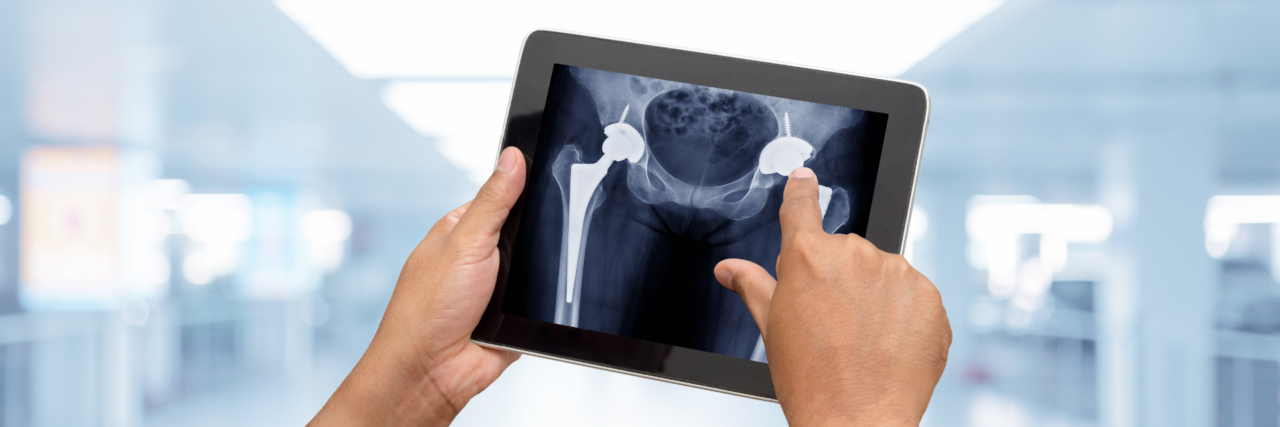

Rothman Orthopaedics' Joint Replacement Program is one of the nation's top joint replacement centers, performing more than 17,000 joint surgeries annually.

The joint replacement team at Rothman Orthopaedic Institute performs more than 9,000 surgeries every year. Each member of the team is specially trained, has extensive experience and is skilled to perform total joint replacements. Every physician that is a part of this outstanding team of doctors has undergone extensive subspecialty training during his/her residency and fellowship. This team is at the cutting edge of new research in the joint replacement field and Rothman physicians are actually responsible for training other orthopaedic surgeons through international lectures, webcasts, and surgical satellite simulcasts.